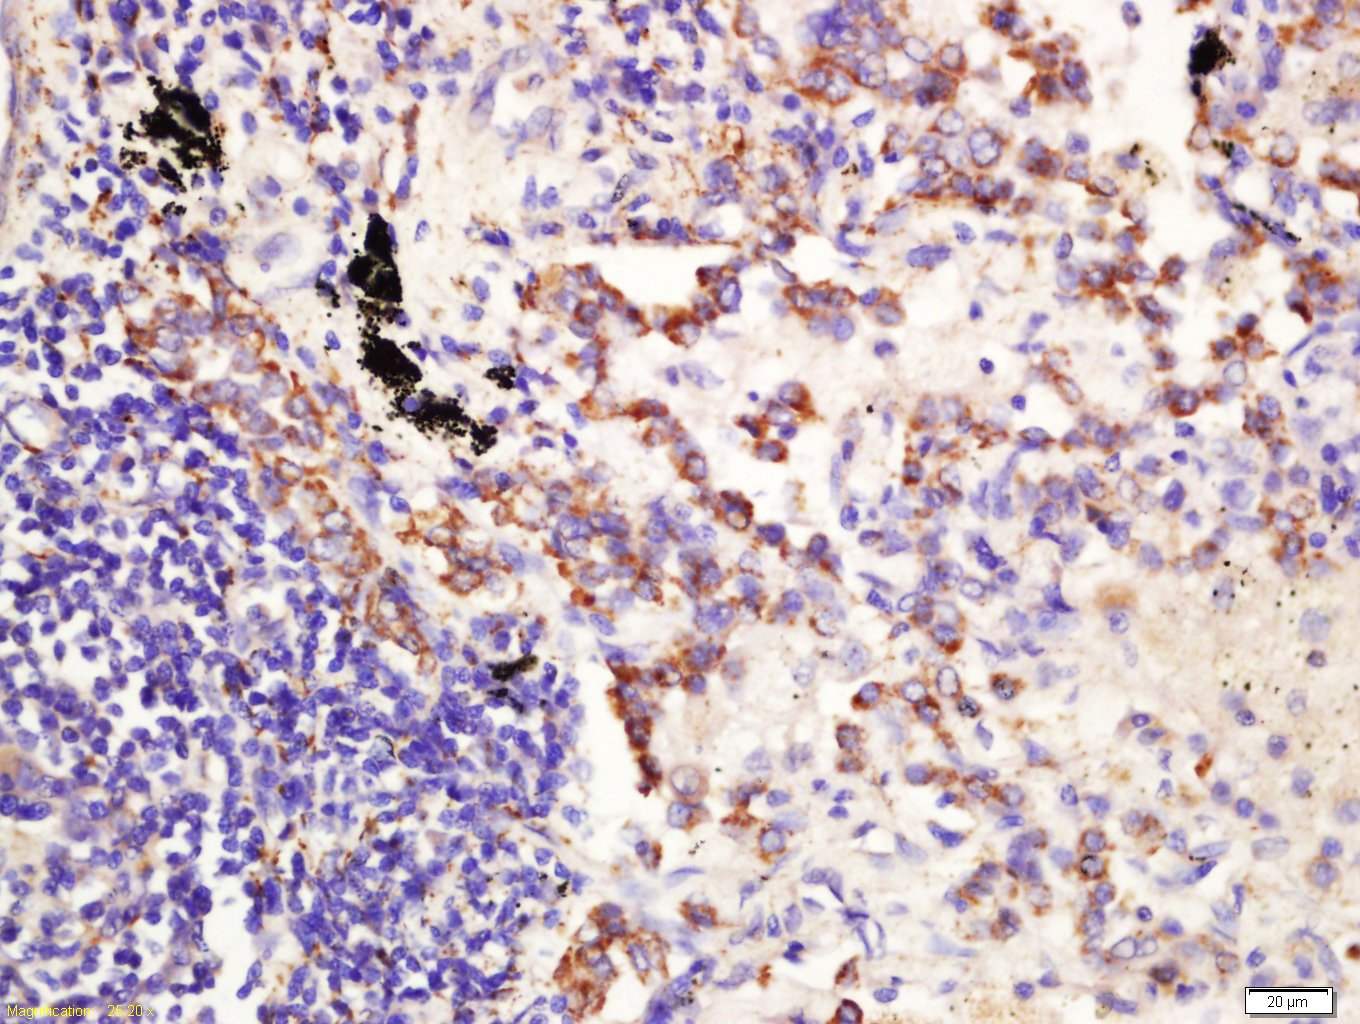

Tissue/cell: Human lung cancer tissue; 4% Paraformaldehyde-fixed and paraffin-embedded; Antigen retrieval: citrate buffer ( 0.01M, pH 6.0 ), Boiling bathing for 15min; Block endogenous peroxidase by 3% Hydrogen peroxide for 30min; Blocking buffer (normal goat serum,C-0005) at 37℃ for 20 min; Incubation: Anti-CD361 Polyclonal Antibody, Unconjugated(bs-14684R) 1:200, overnight at 4°C, followed by conjugation to the secondary antibody(SP-0023) and DAB(C-0010) staining